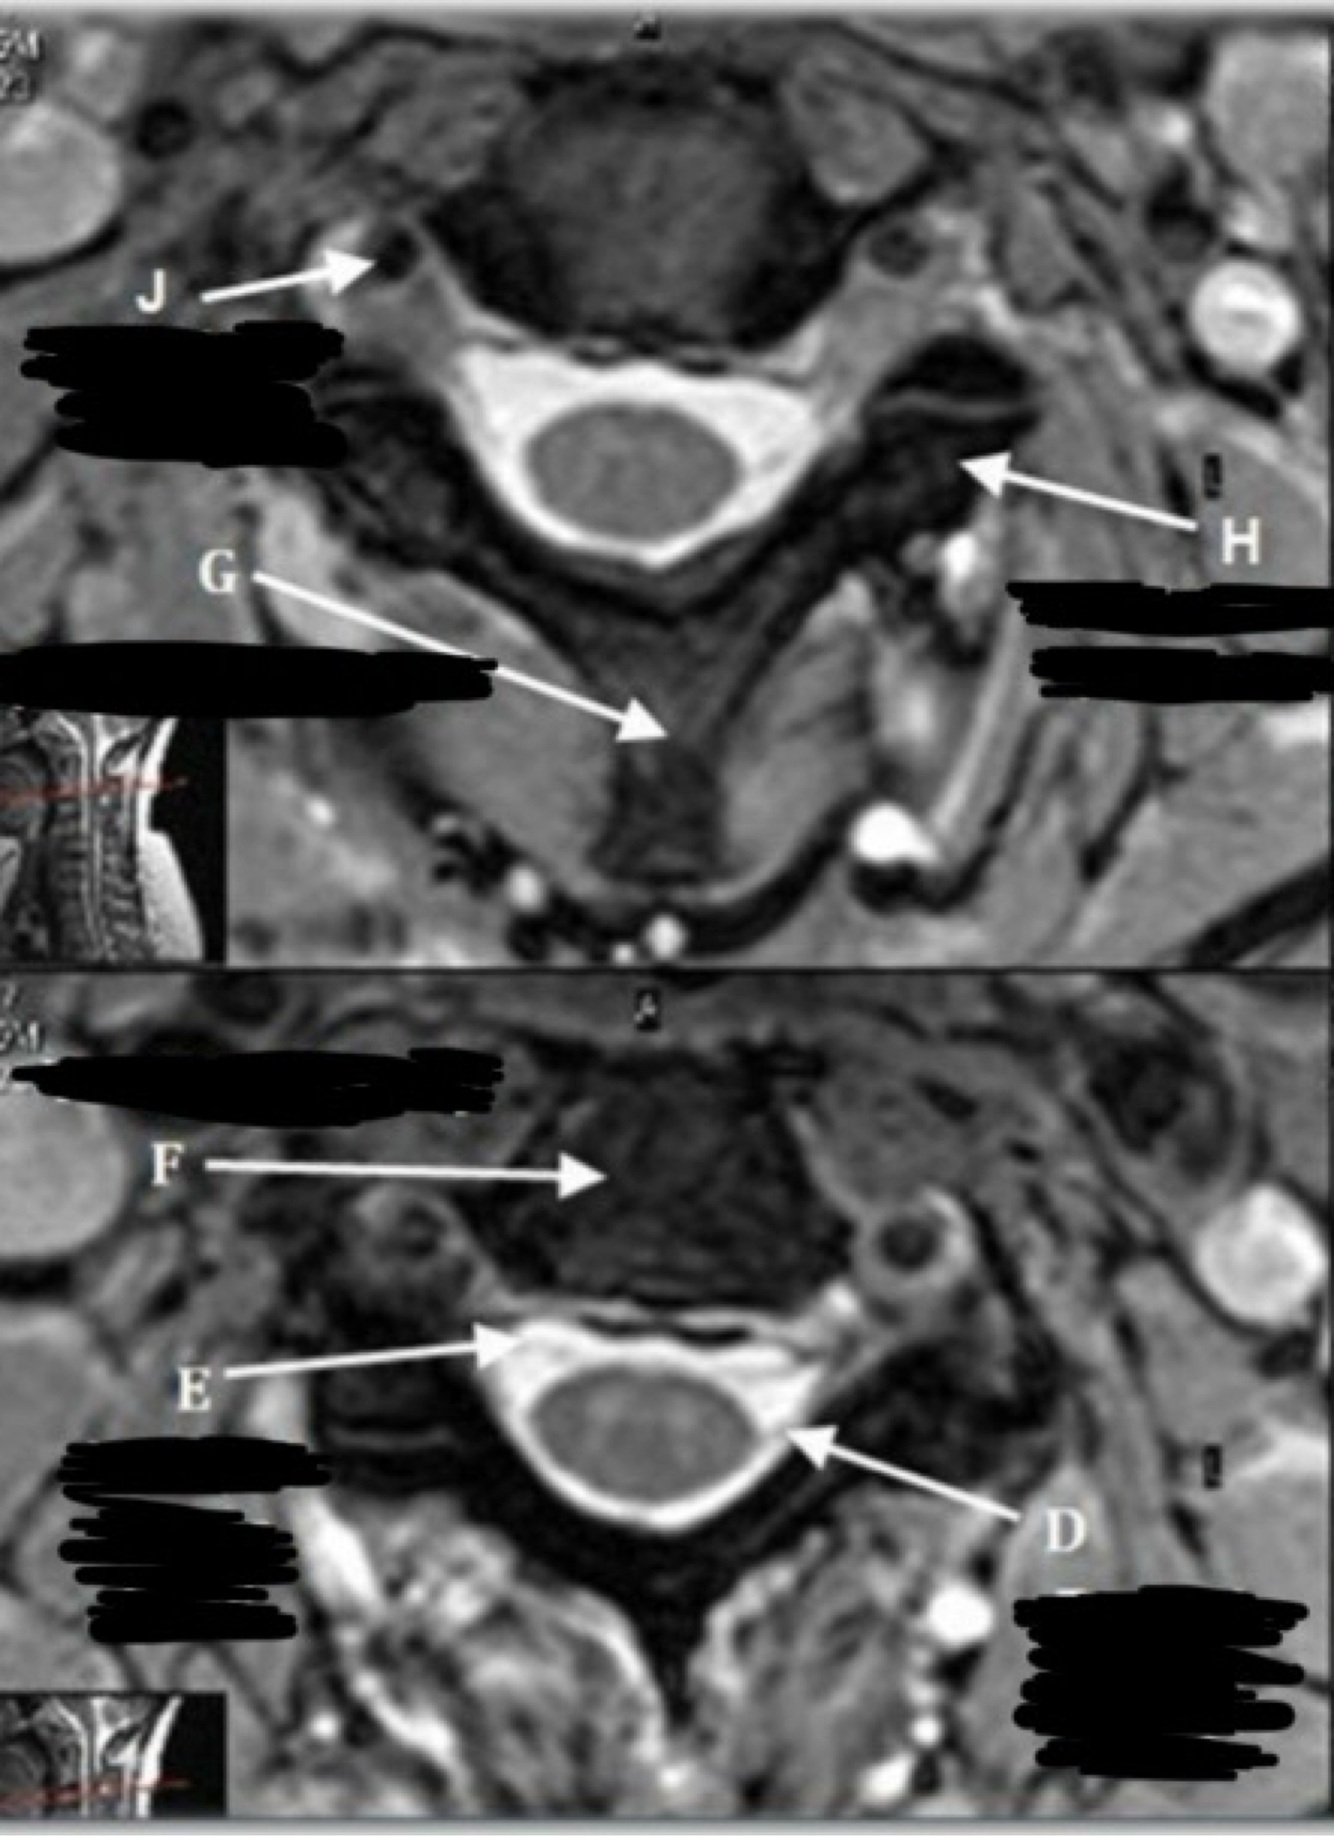

10

What is letter A?

CSF

11

What is letter B?

SPINAL CORD

12

What is letter C?

LAMINA

13

What is letter D?

DORSAL NERVE ROOT

14

What is letter E?

VENTRAL NERVE ROOT

15

What is letter F?

VERTEBRAL BODY

16

What is letter G?

SPINOUS PROCESS

17

What is letter H?

TRANSVERSE PROCESS

18

What is letter J?

VERTEBRAL ARTERY